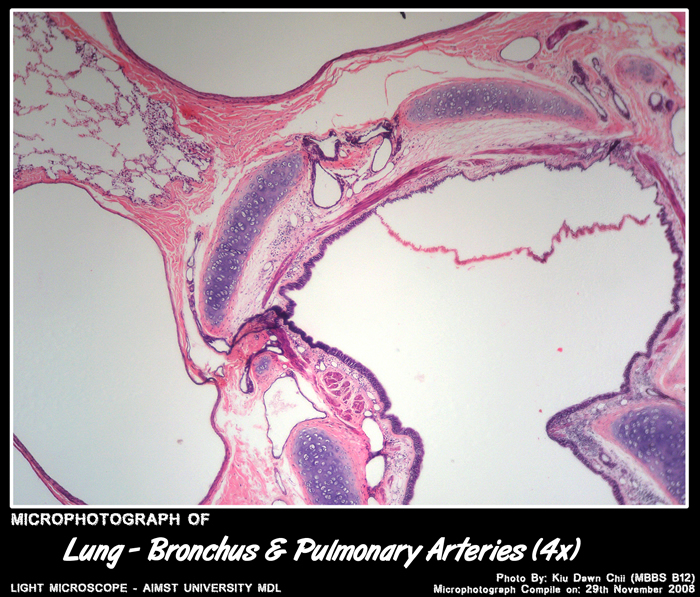

LUNGS

Histology of Bronchi: Primary, secondary, tertiary

• Epithelium – respiratory epithelium – columnar cells have gradual decrease in height, cilia & goblet cells.

• Lamina propria - gradual decrease in thickness & increase in number of elastic fibres.

• Glands – mucous & serous glands .

• Skeletal connective tissue – complete rings in primary, plates of cartilage in smaller bronchi.

• Muscle – several layers of circular smooth muscle.